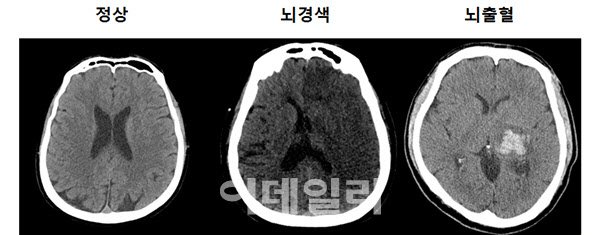

- 신경계 문제(뇌종양, 뇌졸중 등)의 진단

MRI(자기 공명 영상)은 강력한 자기장과 라디오파를 이용하여 체내 조직의 이미지를 생성하는 기술입니다. MRI는 연부 조직, 즉 뇌, spinal cord, 근육, 그리고 다양한 내장 장기 등을 상세하게 볼 수 있는 특징이 있습니다. 주로 신경계, 근골격계 및 종양 연구의 진단 도구로 사용됩니다.